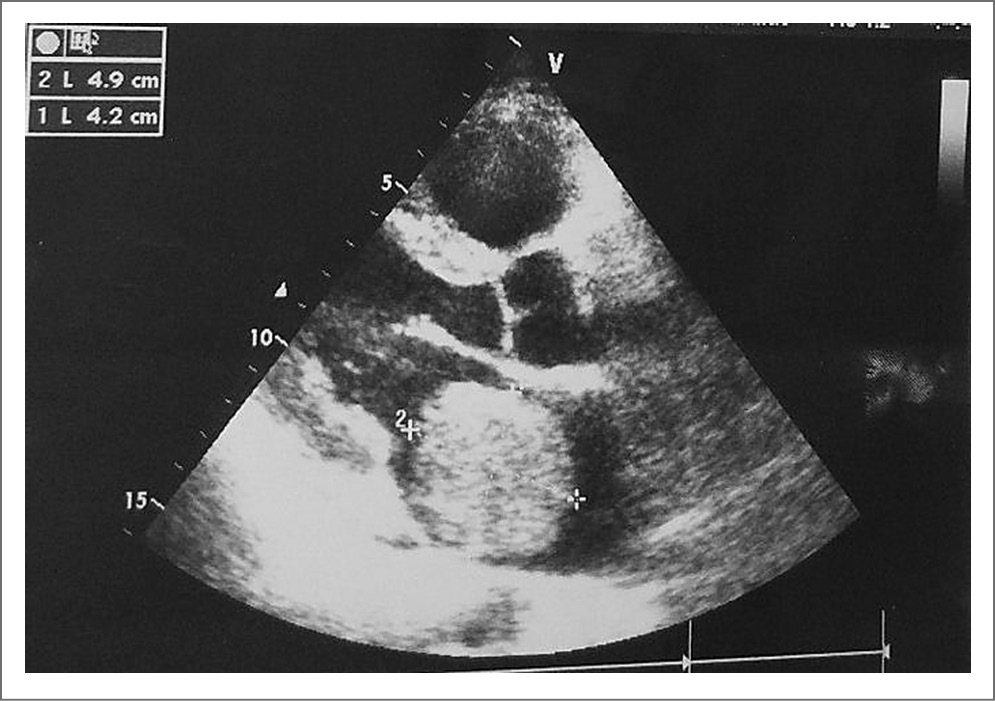

При тщательном расспросе удалось выяснить, что снижение толерантности к физической нагрузке и появление одышки (в основном во время интенсивной физической нагрузки – больной увлекается зимней рыбалкой) стал отмечать в течение последних 5–6 лет. Около 2,5 года назад обратил внимание на постепенное нарастание одышки, а также появление болей в эпигастральной области и правом подреберье, в основном, как больному казалось, после погрешностей в диете. В течение 2017 г. состояние прогрессивно ухудшалось. На фоне постоянно сохраняющейся одышки, слабости и кашля периодически повышалась температура. Неоднократно обращался к врачам, состояние расценивалось как пневмония, проводилась антибактериальная терапия с относительным эффектом. Температура снижалась на какое-то время, общее состояние не улучшалось. К врачам обратился только в январе 2018 г., когда на фоне выраженной физической нагрузки значительно возросли одышка, сердцебиение, усилились боли в правом подреберье, появились отеки ног и увеличение живота в объеме. Так как к одышке больной адаптирован, а на первый план в клинической картине вышли абдоминальные и диспептические жалобы, он обратился к гастроэнтерологу. В общем анализе крови от 27.01.2018 определялись умеренная гипохромная анемия, нормальный уровень лейкоцитов и СОЭ, в биохимическом анализе – повышение уровня глюкозы до 6,90 ммоль/л, мочевины до 8,5 ммоль/л. Остальные параметры биохимического анализа крови оставались в пределах нормальных значений. При ультразвуковом исследовании (УЗИ) брюшной полости от 30.01.2018 выявлены умеренная гепатомегалия, диффузные изменения печени, небольшое утолщение стенок желчного пузыря. Заподозрен острый холецистит, в связи с чем рекомендована госпитализация в стационар, предлагалось оперативное лечение, от которого больной отказался. Состояние продолжало прогрессивно ухудшаться. В основном отмечал усиление болей в правом подреберье, тошноту, рвоту, не приносящую облегчение, отсутствие аппетита, увеличение объема живота. 02.02.2018 при повторной сдаче биохимического анализа крови и коагулограммы уже выявлены существенные изменения в виде снижения уровня общего белка, альбумина, протромбина, повышение уровня общего билирубина за счет прямой фракции, γ-глютамилтранспептидазы, щелочной фосфатазы. В анализах мочи – протеинурия, наличие билирубина, повышение уробилиногена. Пациент вновь обратился за консультацией к гастроэнтерологу. При осмотре обращали на себя внимание увеличение печени (+6 см из-под края реберной дуги), боли в правом подреберье. К этому времени больному дважды в разных медицинских учреждениях проводилось УЗИ брюшной полости, выявлявшее признаки «острого холецистита». Тем не менее пациент вновь срочно направлен на УЗИ органов брюшной полости, где помимо гепатомегалии, утолщения стенок желчного пузыря и наличия небольшого количества свободной жидкости в брюшной полости обратило на себя внимание расширение нижней полой вены до 28–29 мм (норма – до 25 мм), а также при исследовании в режиме спектральной допплерографии в воротной вене определялся аномальный кровоток в виде пульсирующего двунаправленного кровотока, что могло быть связано с повышением давления в правых отделах сердца. Больной срочно направлен на эхокардиографию (ЭхоКГ): выявлено крупное образование в левом предсердии – ЛП (миксома? тромб?), пролабирующее в диастолу в левый желудочек (ЛЖ), расширение всех камер сердца. Полость ЛЖ – 6,0–6,2 см (N – до 5,5 см), конечно-диастолический объем – 105 мл, полость правого желудочка (ПЖ) – 3,0 см (N – до 2,6 см) на боку из парастернального доступа, 4,8 см из апикального доступа (N – до 3,5 см), предсердий – значительное (левое 5,0×7,3×6,1 см – 156 мл, правое – 7,0×5,5 см – 129 мл) [по Simpson], расширение ствола легочной артерии – 3,0 см, значительная легочная гипертензия (среднее давление в легочной артерии – СДЛА 78,5 мм рт. ст.), трикуспидальная недостаточность и легочная недостаточность 2–3-й степени, митральная недостаточность 1-й степени (рис. 1).

Рис. 1. ЭхоКГ: крупное образование в ЛП (миксома? тромб?), пролабирующее в диастолу в ЛЖ